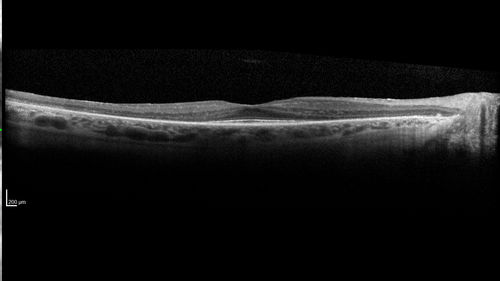

Retinitis Pigmentosa - Autosomal Dominant - Good Vision

55 year old female was diagnosed in 1990 with RP and the vision has been stable for the last 10 years.  Her mother and her two brothers and her grandmother and the patient and her two sisters all have confirmed RP.  No one has been tested. VA 20/25 OU